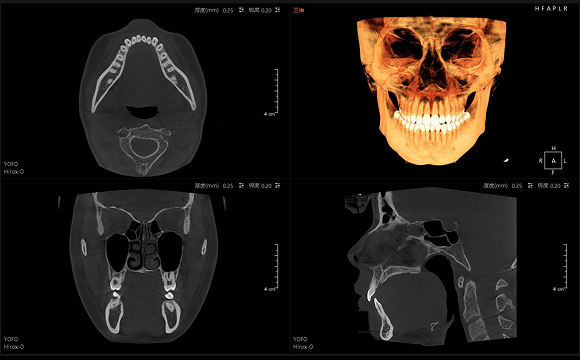

• CT

CT

3D 正側位

• 3D TMJ視圖

3D TMJ視圖

只需一次單圈掃描即可獲得CT、數字全景和3D正/側位影像,

并能同時生成3D TMJ視圖 提高診療效率,避免過度檢查,減少患者所受的輻射